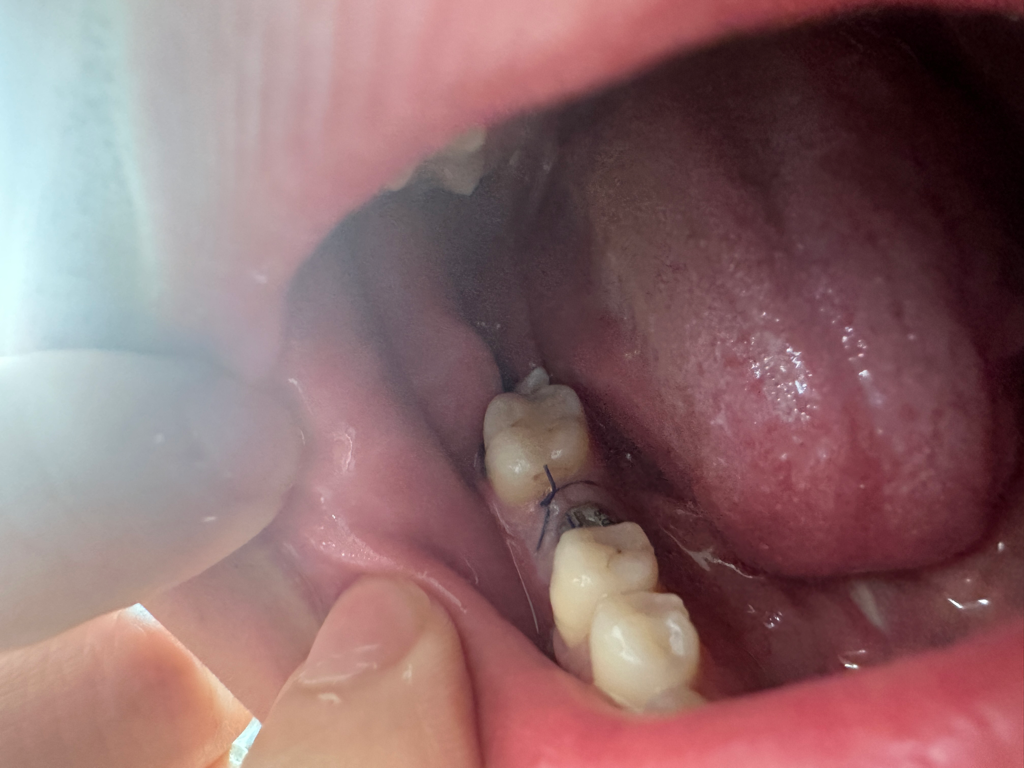

매복 사랑니 발치6일차인데 무슨 뼈 같은게 보여요

매복사랑니 발치한 부분 꿰맨 부분 옆으로

무슨 뼈같은게 튀어나와있고 좌우로 막 움직입니다

임플란트하면서 매복사랑니도 빼고 꿰맨건데;;

이 하얀거 막 건드리면 움직이는데 손으로 그냥 뽑아도 되나요 ㅠㅠ? 좌우로 움직여서 거슬려요..